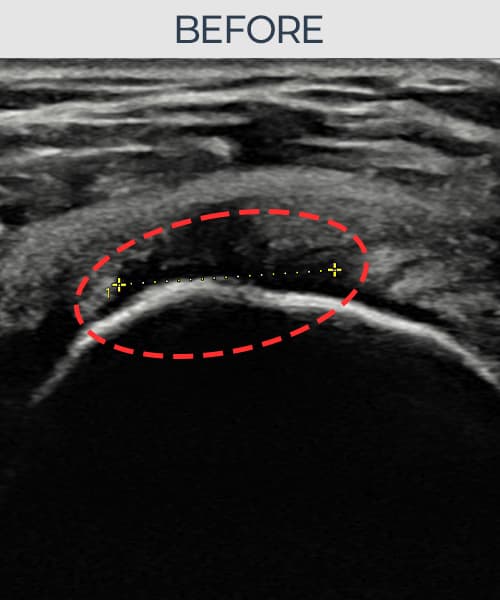

超声确认旋转肌腱袖 关节面侧撕裂(9mm × 5mm (肌腱厚度约50%缺损))。缩小缝合术后肌腱连续性恢复,患者回归正常生活。

术前

术前超声确认旋转肌腱袖 关节面侧撕裂,冈上肌腱回声不连续伴肌腱缺损(9mm × 5mm (肌腱厚度约50%缺损))。术后超声显示撕裂部位充满再生组织,肌腱连续性恢复,回声模式正常化。

该患者持续肩痛。详细超声检查确认旋转肌腱袖 关节面侧撕裂(缺损:9mm × 5mm (肌腱厚度约50%缺损))。在超声引导下实施非手术缩小缝合术。术后佩戴支具约4-6周,随后进行分阶段康复锻炼。随访超声确认肌腱连续性恢复、结构稳定,患者顺利回归日常生活。